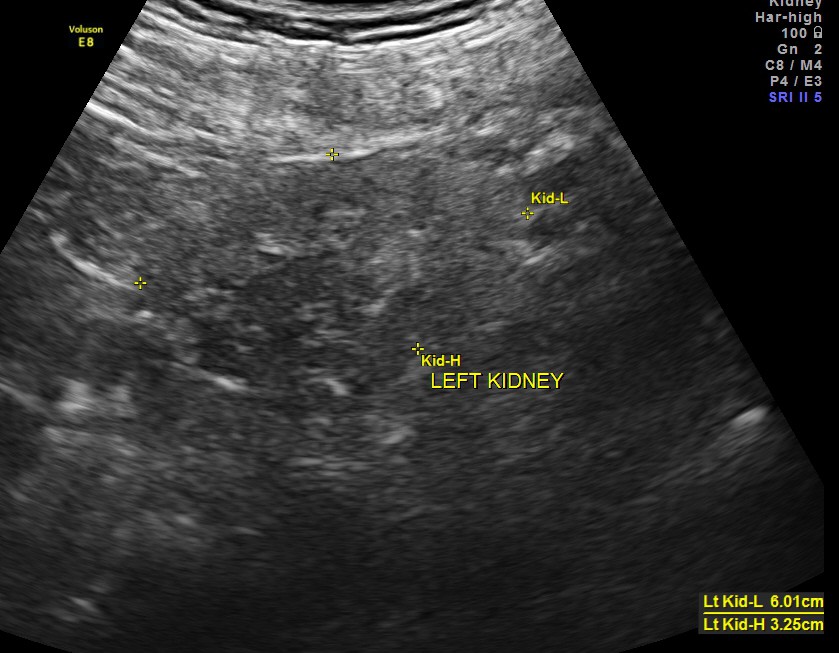

Both kidneys show features of medical renal disease.